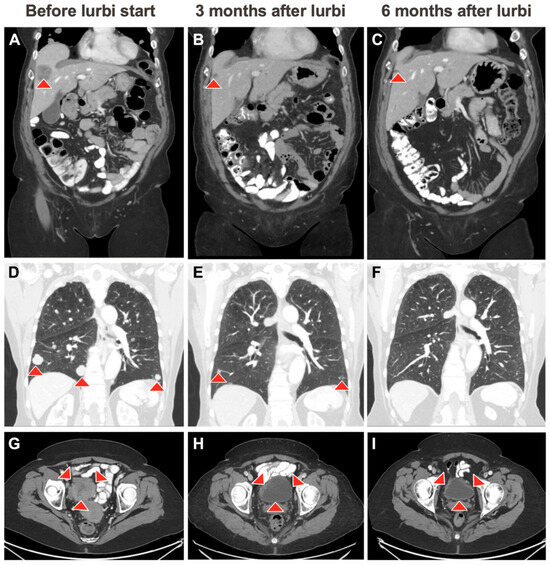

2. Case Description